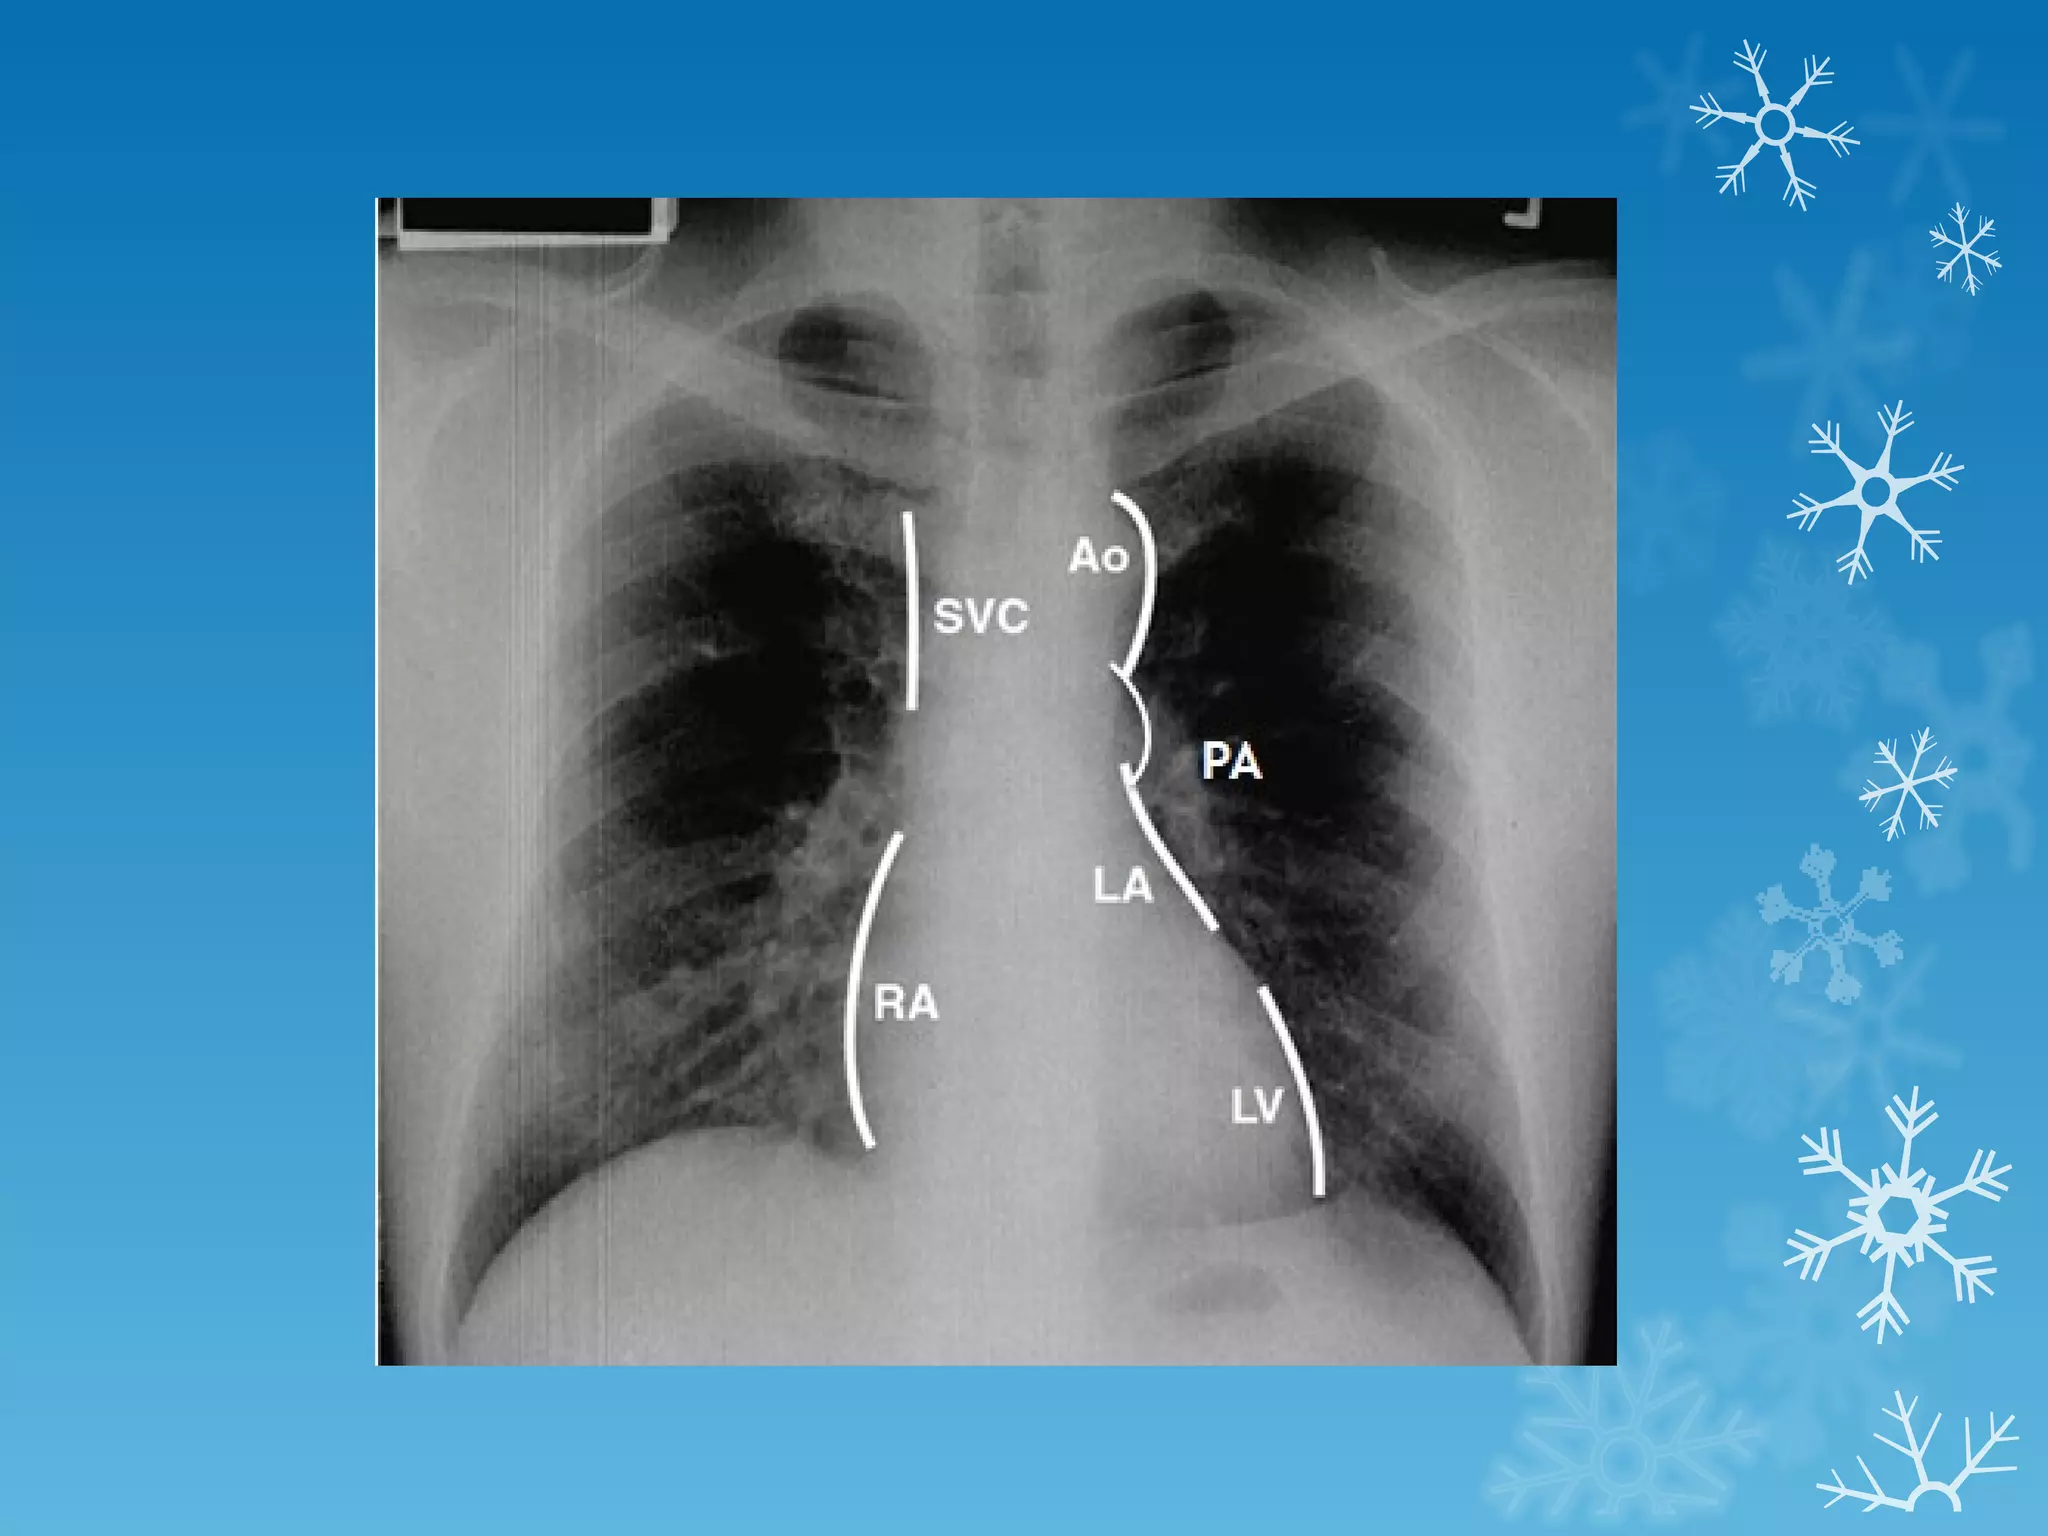

This document discusses chest x-ray interpretation and provides guidance on evaluating x-rays. It explains that tissue density determines how an x-ray beam penetrates, with denser tissues appearing whiter and less dense tissues appearing blacker. It also outlines different chest x-ray views and factors to consider like patient orientation, age, gender, and rotation. Abnormalities are described as appearing too white, too black, too large, or in the wrong place. The document stresses a systematic approach of identifying, localizing, describing lesions, and providing differential diagnoses.